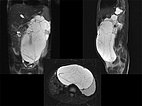

Fat-saturated, T2-weighted MRI in three planes reveals the cause: retroperitoneally located giant cysts due to a macrocystic lymphatic malformation.